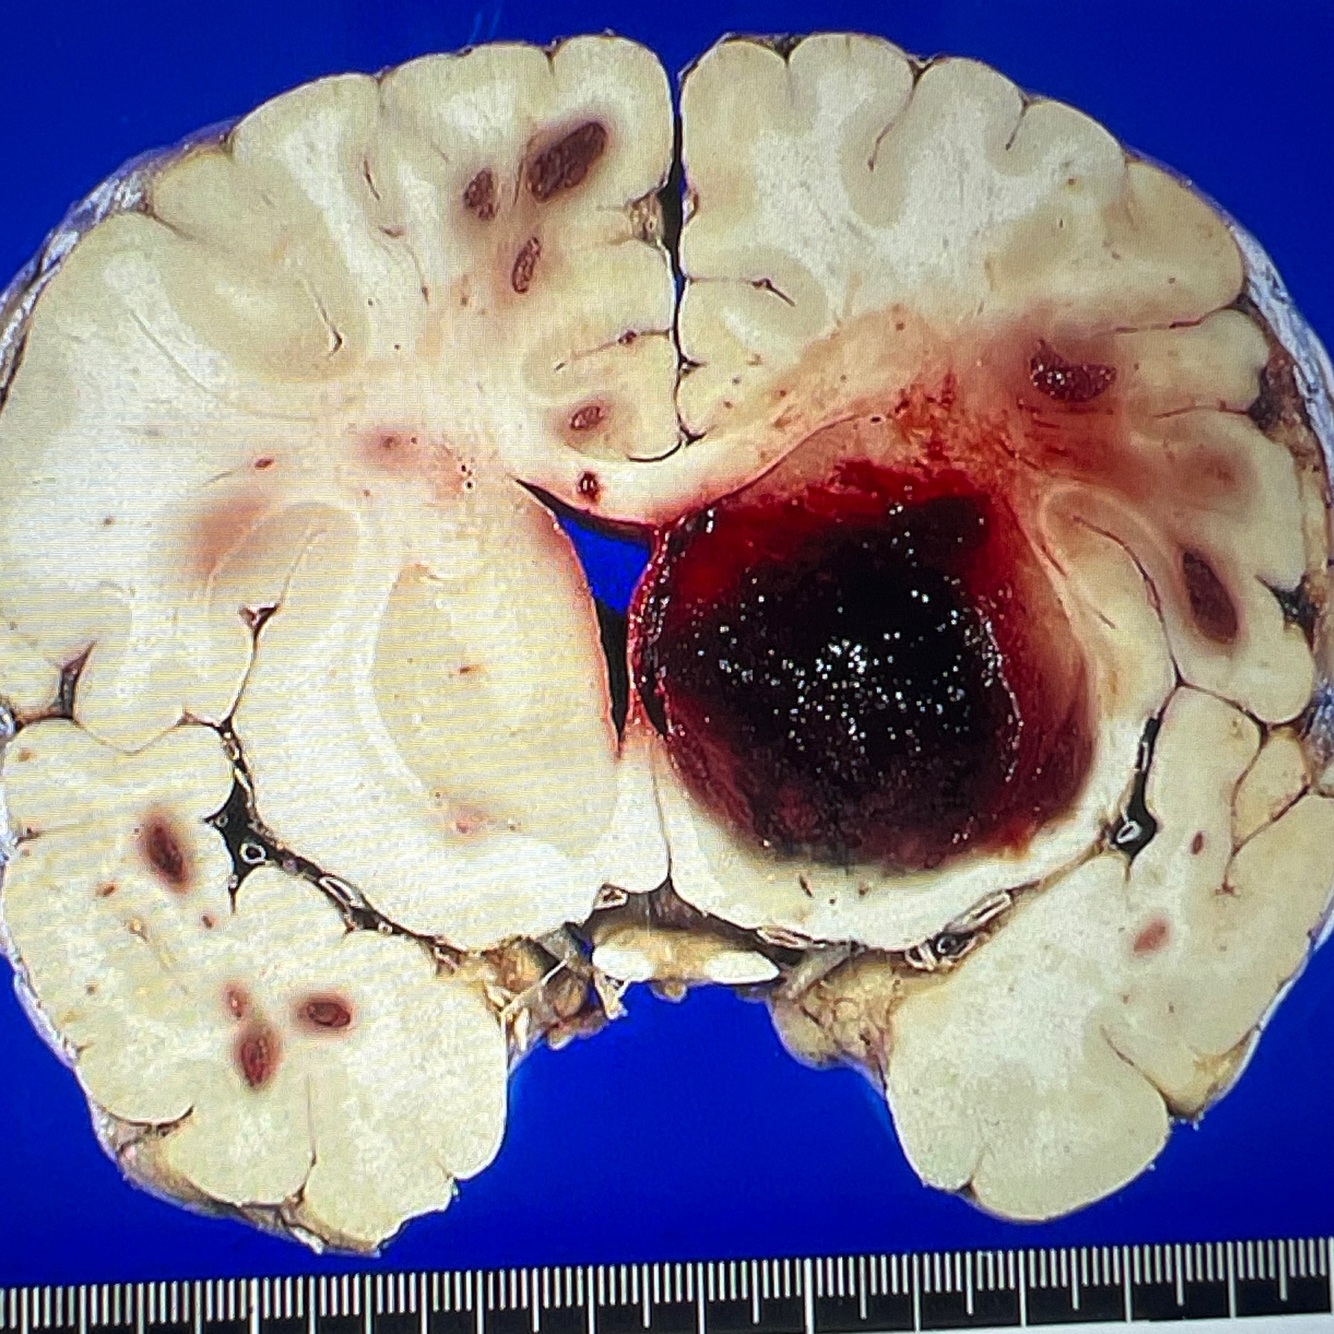

Diagnosis: intracerebral hemorrhage

Location: basal ganglia

A coronal section in the brain showing a localised area of large dark red brown hematoma in the cerebral hemisphere

Note compression effects on the ventricle

Smaller hemorrhagic foci are also seen